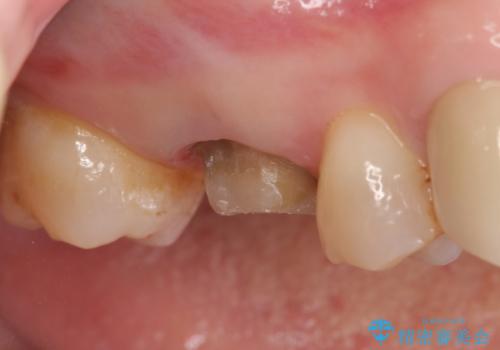

- 右上の奥歯でものを咬むと痛むため他院を受診したが、治療は難しいと言われたため当院にいらっしゃった方の症例です。

再根管治療を行い症状の緩解を確認後、オールセラミッククラウンによる補綴を行いました。